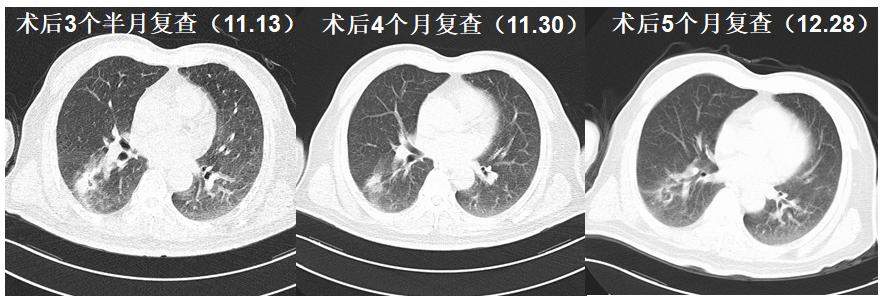

术后影像学检查

1. 载药微球化疗栓塞,患者耐受性好,缓解临床症状,提高生活质量。

2. 联合免疫治疗达到不错的疗效。